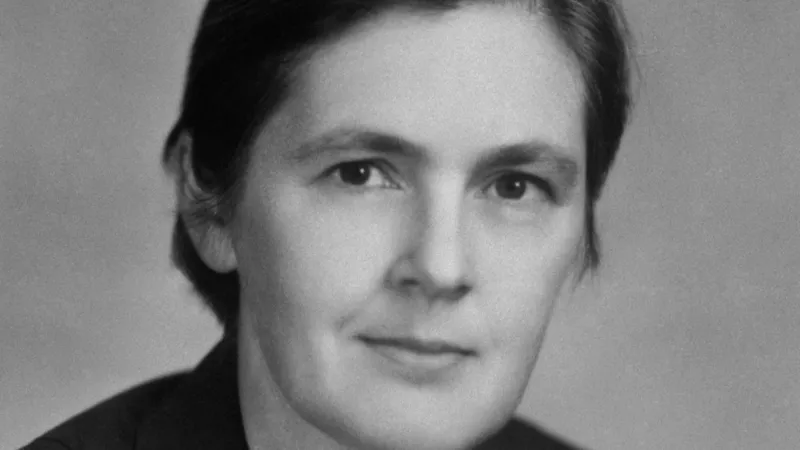

Frances Oldham Kelsey murió en 2015 a los 101 años.

El científico había confundido “el nombre Frances por el masculino Francis”, contaron Adam Bernstein y Patricia Sullivan, del Washington Post, en el obituario de Kelsey, quien murió en 2015 a los 101 años.

Años después Kelsey bromearía sobre ese episodio y diría que “si su nombre hubiese sido Elizabeth o Mary Jane su carrera pudo haber terminado ahí”.